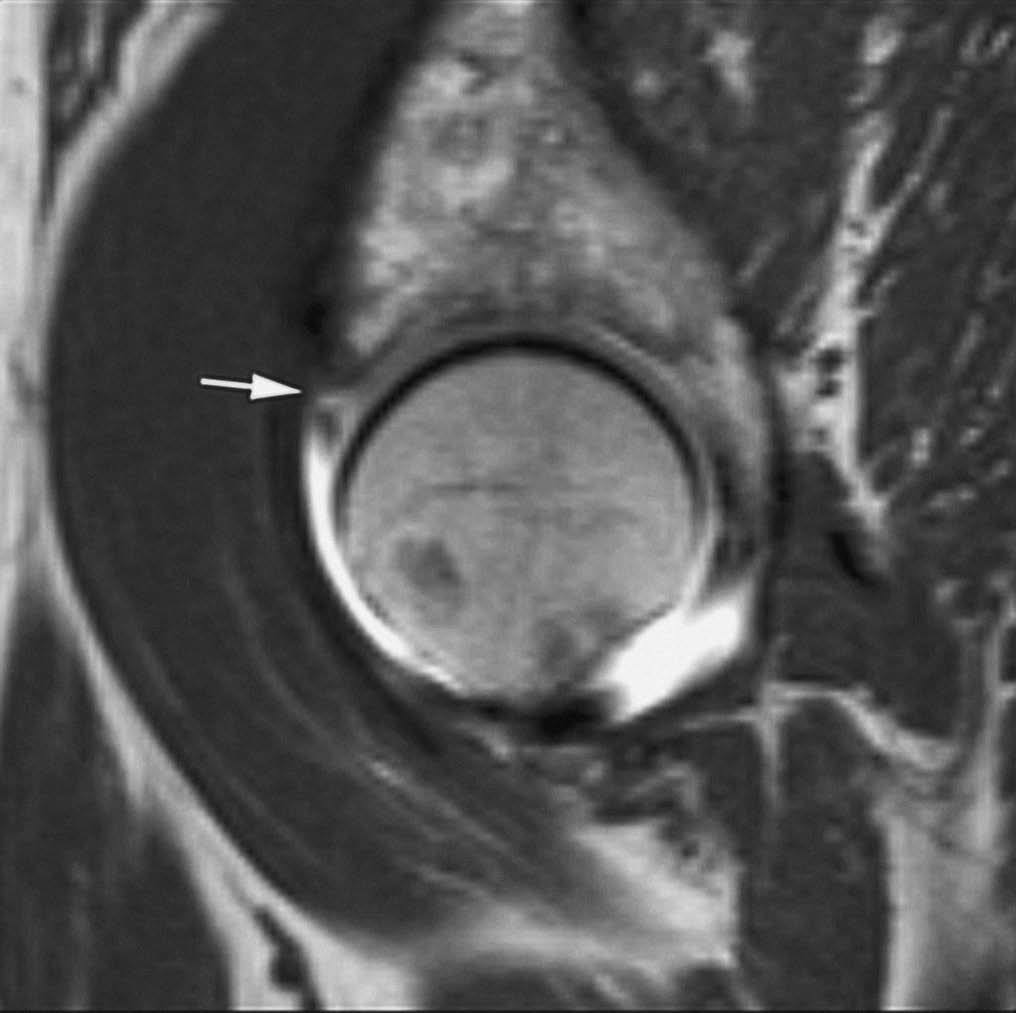

El síndrome del anillo acetabular debería sospecharse a partir de la exploración clínica. La rotura labral actúa como punto de inicio del proceso degenerativo articular. La distribución de las fuerzas a lo largo de la superficie articular se altera y condiciona un impacto repetido de la cabeza femoral en el acetábulo, con desarrollo de defectos condrales y osteoartritis progresiva3,6-10. La RMA permite una valoración precisa de estas lesiones con una excelente correlación con los hallazgos artroscópicos y quirúrgicos. Las roturas displásicas afectan la región superior del labrum, donde es más susceptible al choque repetido con la cabeza femoral (fig. 3). La asociación de las roturas labra les con gangliones quísticos es frecuente en este tipo de pacientes3,8.

Fig. 3.--Displasia de cadera del adulto. Corte axial oblicuo de RMA potenciado en T1 con técnica de supresión grasa. Defecto lineal en el labrum antero-superior (flecha).